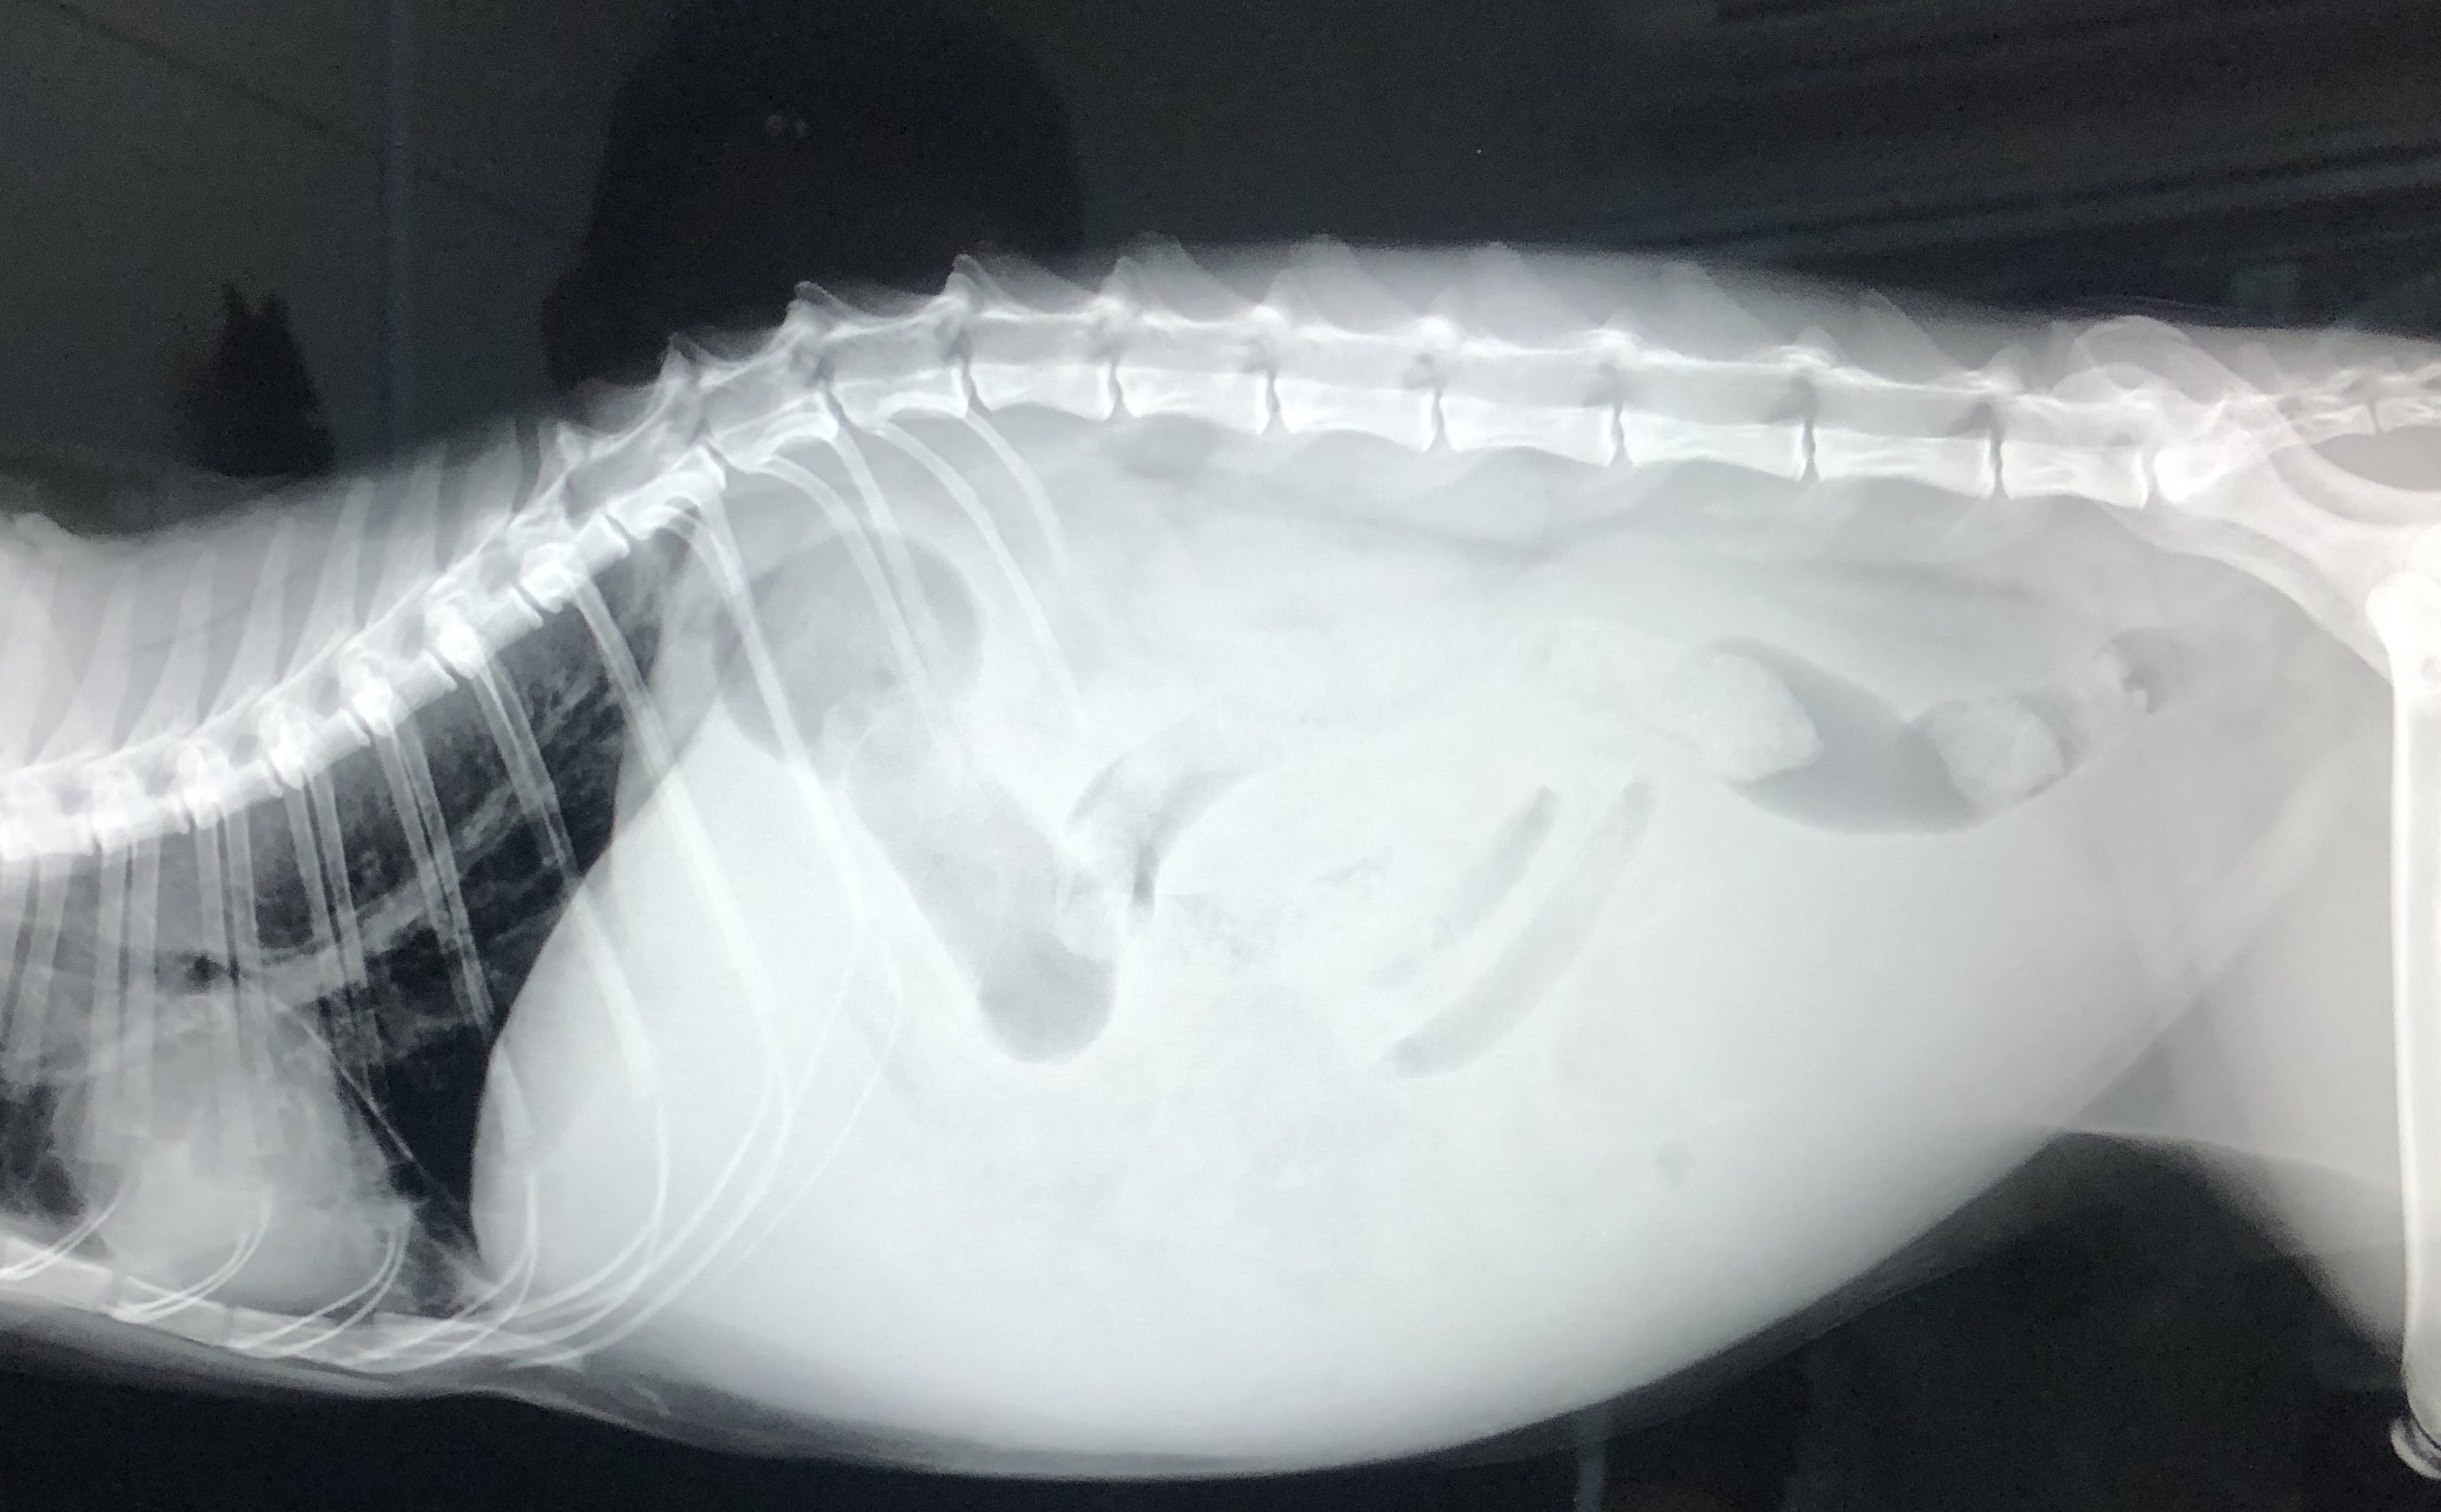

FIPという診断を受けた時に、あらゆる手段を使いこの病気について調べました。動物病院の先生やネットで調べた結果、外猫・野良猫のほとんどが持っているコロナウイルスが突然体内で変異し、FIPウイルスになるということが分かりました。FIPウイルスは一度発症してしまうと元に戻ることはありません。原因はストレスのことが多いと言われており、ずら丸にストレスを与えてしまっていたと日々嘆くばかりです。現在の症状としては腹水・胸水の貯留、食欲減退、便秘、黄疸、脱水症状です。動物病院への通院で脱水症状については収まりを見せていますが、その他は改善の兆しが見えてきません。

腹部レントゲン画像